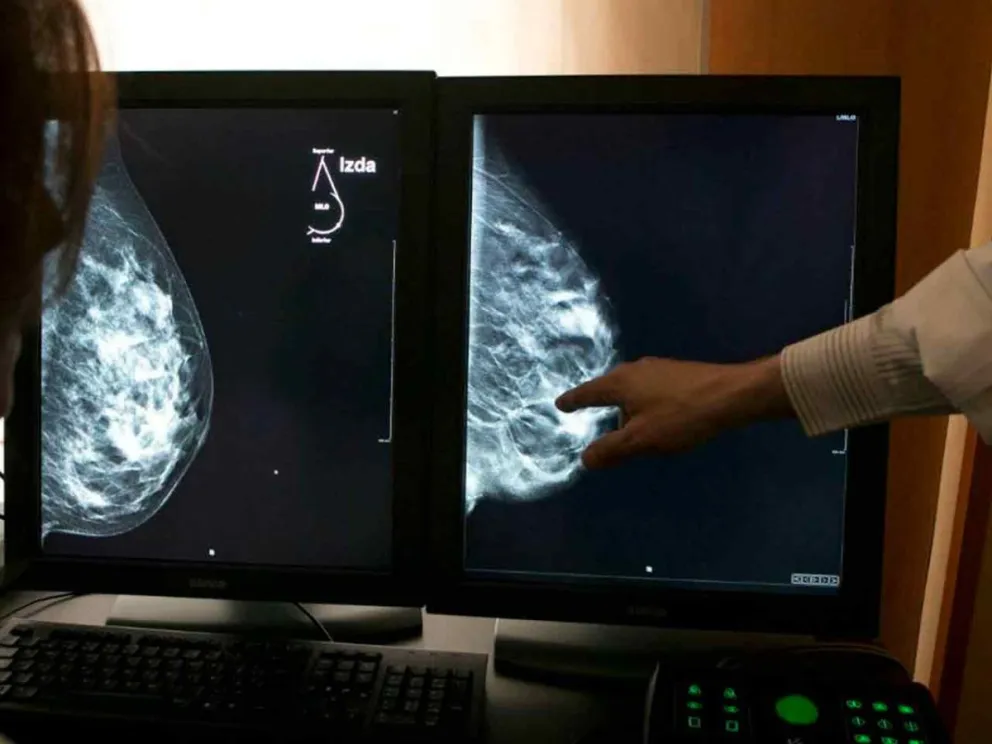

Mes Rosa: Misiones cuenta con múltiples centros de salud pública donde realizarse mamografías de forma gratuita

Destacaron el abordaje multidisciplinario que tiene el Parque de la Salud en la prevención y tratamiento del cáncer de mama